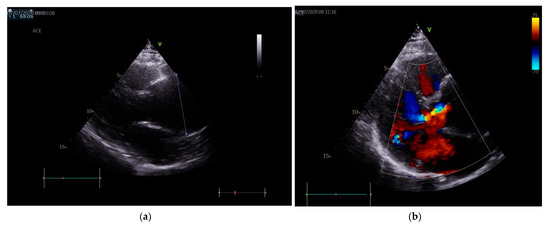

2. Case Presentation